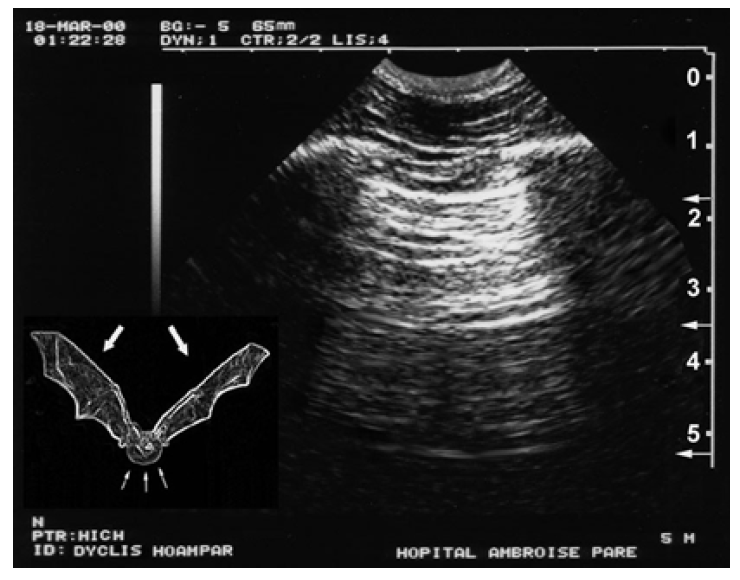

फेफड़े की सतह, यानी, आंतरिक फुफ्फुसावरण, सामान्य रूप से पार्श्विका फुफ्फुसावरण के विपरीत होती है, और दोनों सामान्य विषयों में फुफ्फुस रेखा बनाते हैं। यह मानक वयस्कों में पसली रेखा से एक सेमी से भी कम दूरी पर दिखाई देने वाली रेखा है। यह दूरी मोटे तौर पर 1/2 सेमी आगे की ओर, थोड़ी अधिक पीछे की ओर होती है। नवजात शिशुओं सहित किसी भी उम्र में, फुफ्फुस रेखा दो पसली सीमाओं के बीच की दूरी के लगभग 1/4–1/3 पर स्थित होती है। फुफ्फुस रेखा एक हाइपरइकोइक, मोटे तौर पर क्षैतिज रेखा के रूप में दिखाई देती है (जब जांच सही ढंग से लागू की जाती है, स्पर्शरेखीय), वास्तव में छवि के आंतरिक विरूपण के कारण थोड़ा मुड़ी हुई होती है (क्षेत्रीय और रैखिक जांच के साथ दिखाई देती है)। फुफ्फुस रेखा किसी भी परिस्थिति में दिखाई देनी चाहिए, विशाल सर्जिकल वातस्फीति को छोड़कर (अंजीर 1).

चित्र 1 चमगादड़ का चिह्न। दायाँ ऊर्ध्वाधर पैमाना सेंटीमीटर का है। पसलियाँ (सेमी 1) अपनी धनुषाकार आकृति और स्पष्ट पश्च ध्वनिक छाया से पहचानी जाती हैं। पसली रेखा (वयस्कों में 1/2 सेमी) के नीचे एक क्षैतिज रेखा (1.75 सेमी) रेखांकित है। यह फुफ्फुस रेखा है, जो मूल रूप से पार्श्विका फुफ्फुस (और आमतौर पर आंतरिक फुफ्फुस) को दर्शाती है। ऊपरी पसली, फुफ्फुस रेखा और निचली पसली हमारी ओर उड़ते हुए एक प्रकार के चमगादड़ का आकार बनाती हैं, इसलिए इसे चमगादड़ का चिह्न कहा जाता है, जो फेफड़ों के अल्ट्रासाउंड में एक बुनियादी चिह्न है। इसे सुरक्षित रखने के लिए हमने यह आकृति बिना तीर के बनाई है।

2. फुफ्फुस रेखा और चमगादड़ चिन्ह

ऊपरी पसली (बायां पंख), प्ल्यूरल लाइन (पेट) और निचली पसली (दायां पंख) द्वारा बनाए गए पैटर्न को बैट साइन नाम दिया गया है, जो किसी भी फेफड़े के अल्ट्रासाउंड में बुनियादी पहला कदम है। यह एक स्थिर लैंडमार्क का उपयोग करके फेफड़ों की सतह का सटीक पता लगाने की अनुमति देता है। अनुदैर्ध्य स्कैन का उपयोग करते हुए, प्ल्यूरल लाइन हमेशा नियंत्रण में रहती है, कठिन परिस्थितियों में भी। चमगादड़ साइन की अवधारणा अन्य सभी क्षैतिज हाइपरइकोइक लाइनों, यानी सतही एपोन्यूरोसिस या गहरी पुनरावृत्ति लाइनों (ए-लाइन्स, सब-ए-लाइन्स, नीचे देखें) के साथ भ्रम से बचाती है। वयस्कों में दो रिब शैडो (चमगादड़ का पेट) के बीच प्ल्यूरल लाइन की दृश्यमान लंबाई लगभग 2.5 सेमी है (चूंकि सेक्टोरियल स्कैन की अवधारणा एक त्रिकोणीय छवि बनाती है